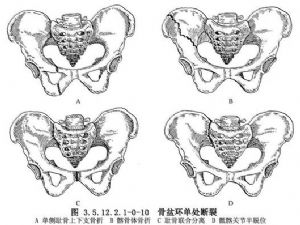

2.骨盆環單處骨折(Ⅱ型) 包括單側恥骨上下支骨折、髂骨體骨折、恥骨聯合輕度分離與骶髂關節半脫位(圖3.5.12.2.1-0-10)。這類骨折僅在一處造成骨盆環的連續性中斷,骨盆環仍較穩定,骨折亦多無明顯移位。恥骨聯合分離和骶髂關節半脫位整復後,應用外固定器固定可早期離牀活動,減少臥牀和避免用骨盆兜帶懸吊或用石膏褲之苦。